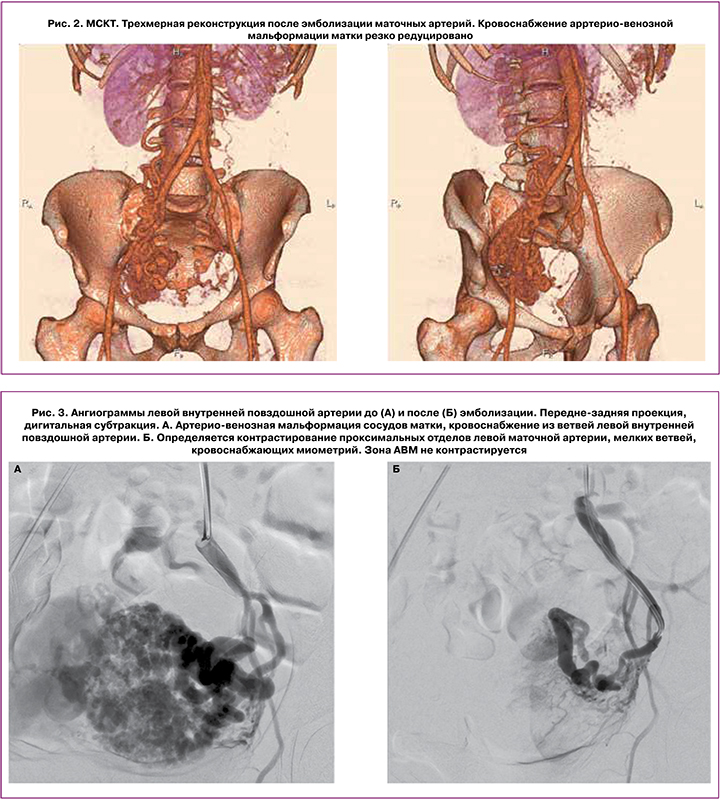

По результатам исследования проведена консультация ангиохирурга, выполнена технически успешная двусторонняя ЭМА, ветвей внутренних подвздошных артерий. Описание операции: под местной анестезией раствором новокаина пунктирована правая бедренная артерия. Установлен интродьюсер 5F. Катететром С2 катетеризирована правая почечная и правая добавочная почечная артерии. Выполнена ангиография. Отмечено кровоснабжение правой яичниковой артерии из измененных ветвей почечных артерий справа. Пупочный артериальный катетер проведен в левую и правую внутренние подвздошные артерии, выполнена ангиография. На ангиограммах отмечается контрастирование обширной зоны патологической васкуляризации в проекции малого таза. Питание осуществляется из маточной артерии слева, маточной артерии справа (определяется крупная артерио-венозная фистула с преимущественным сбросом контрастного препарата в подвздошные вены справа), ветвей внутренней подвздошной артерии справа. Выполнена ЭМА слева цилиндрическими эмболами, маточной артерии справа спиралью 14 см × 15 мм, ветвей внутренней подвздошной артерии справа цилиндрическими эмболами.

На контрольных ангиограммах кровоснабжение патологического сосудистого сплетения резко редуцировано. Катетер и интродьюсер удалены, компрессионный гемостаз, наложена асептическая давящая повязка. Использовано эмболизирующего материала: цилиндры (ААА 750 мкм × 10 мм) – 8 фл., цилиндры (ААА 600 мкм × 10 мм) – 1 фл. Эффективная эквивалентная доза: 1,37 мЗв. Использовано контрастного препарата: 600 мл (рис. 3, 4).